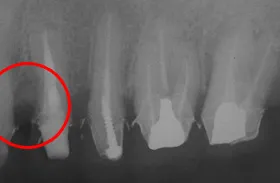

■治療後

術前に比べ、歯茎の組織が再生され、健康な状態の時とほぼ同様になりました。

■歯槽骨再生治療後